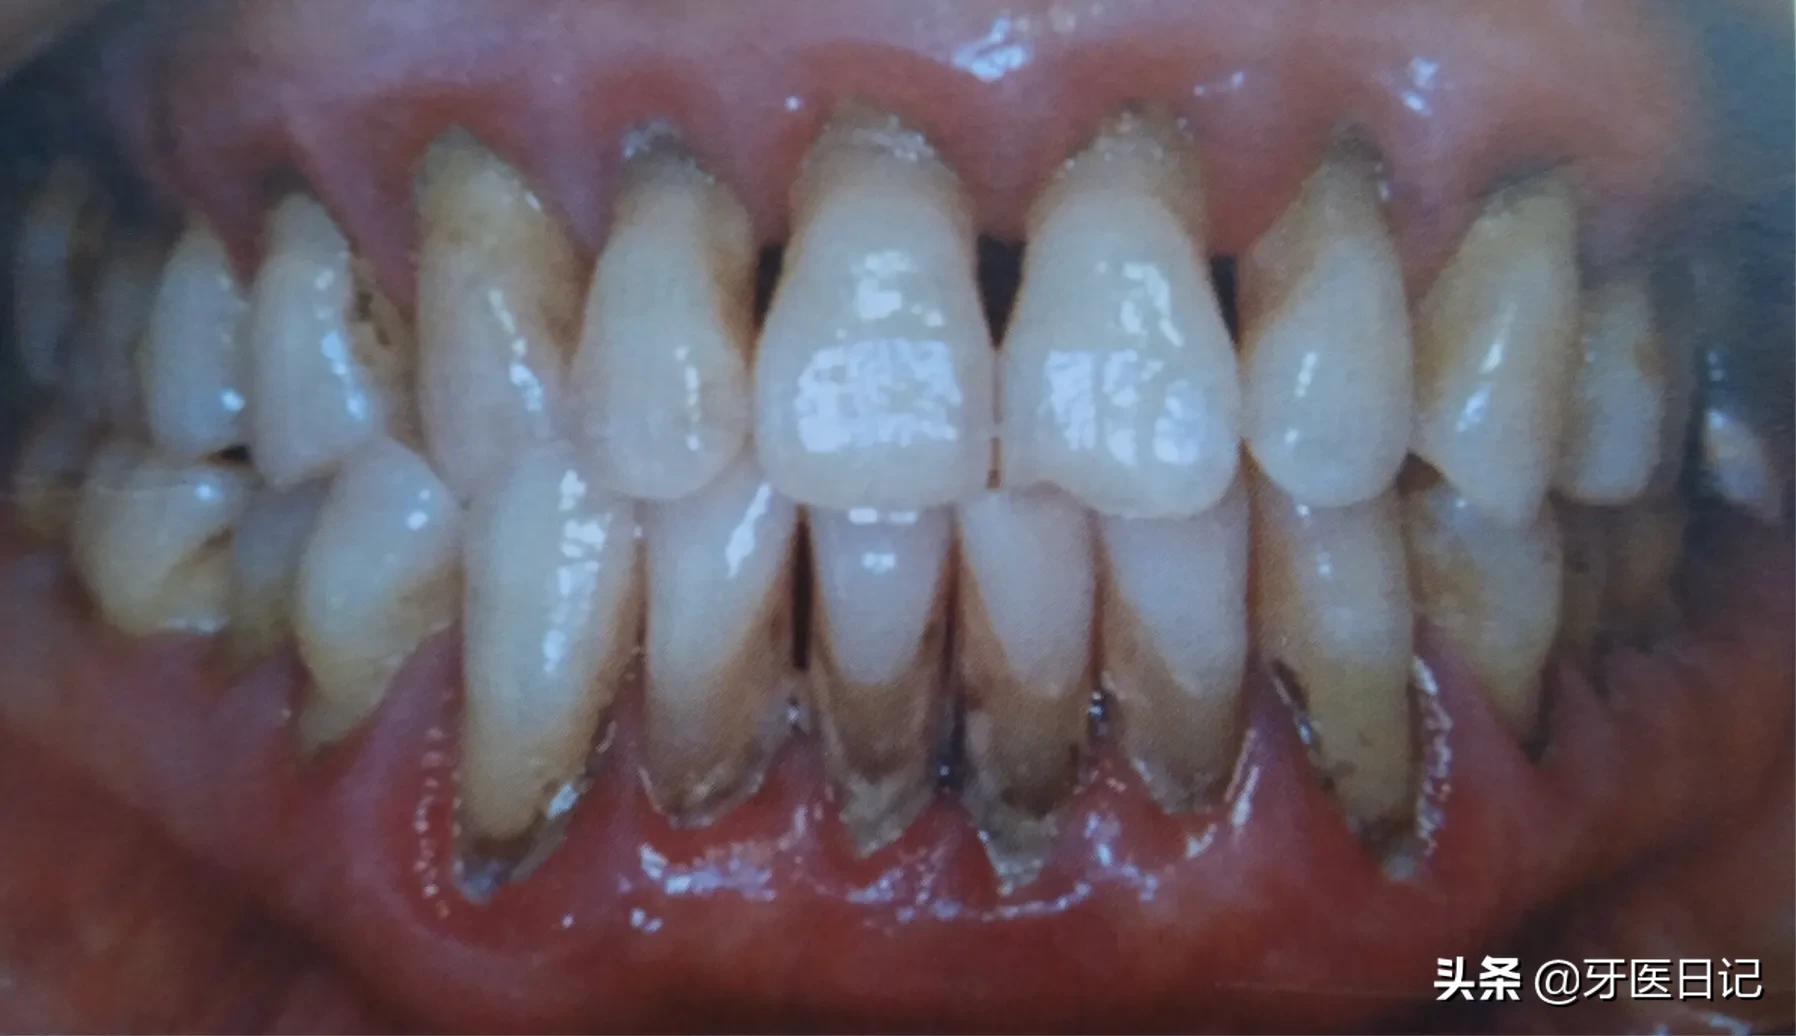

首先就是牙龈的红肿、出血(刷牙时、咬硬物时),其次还有牙龈溢脓、糜烂等

最常见的是口腔卫生不洁,有牙结石的存在,牙结石压迫刺激牙龈,导致牙龈红肿、出血,特别在青春期的同学,或者孕期的女性常会因激素水平的改变而出现青春期牙龈炎和妊娠期牙龈炎,其主要表现就是牙龈红肿和出血,而普通人的牙龈红肿出血多是牙结石刺激导致,当然一些系统疾病也会导致牙龈出血,如白血病。

②牙周炎:主要表现牙齿的松动、移位,牙龈出血,牙槽骨的吸收,同时会伴有牙周袋溢脓口臭等表现

一部分牙龈炎的患者得不到及时治疗,炎症可向牙周深部发展,导致牙齿周围的支持丧失,比如牙齿周围的骨头,随着病变继续向牙根发展,逐渐出现牙齿松动移位,牙龈萎缩,急性肿胀疼痛。